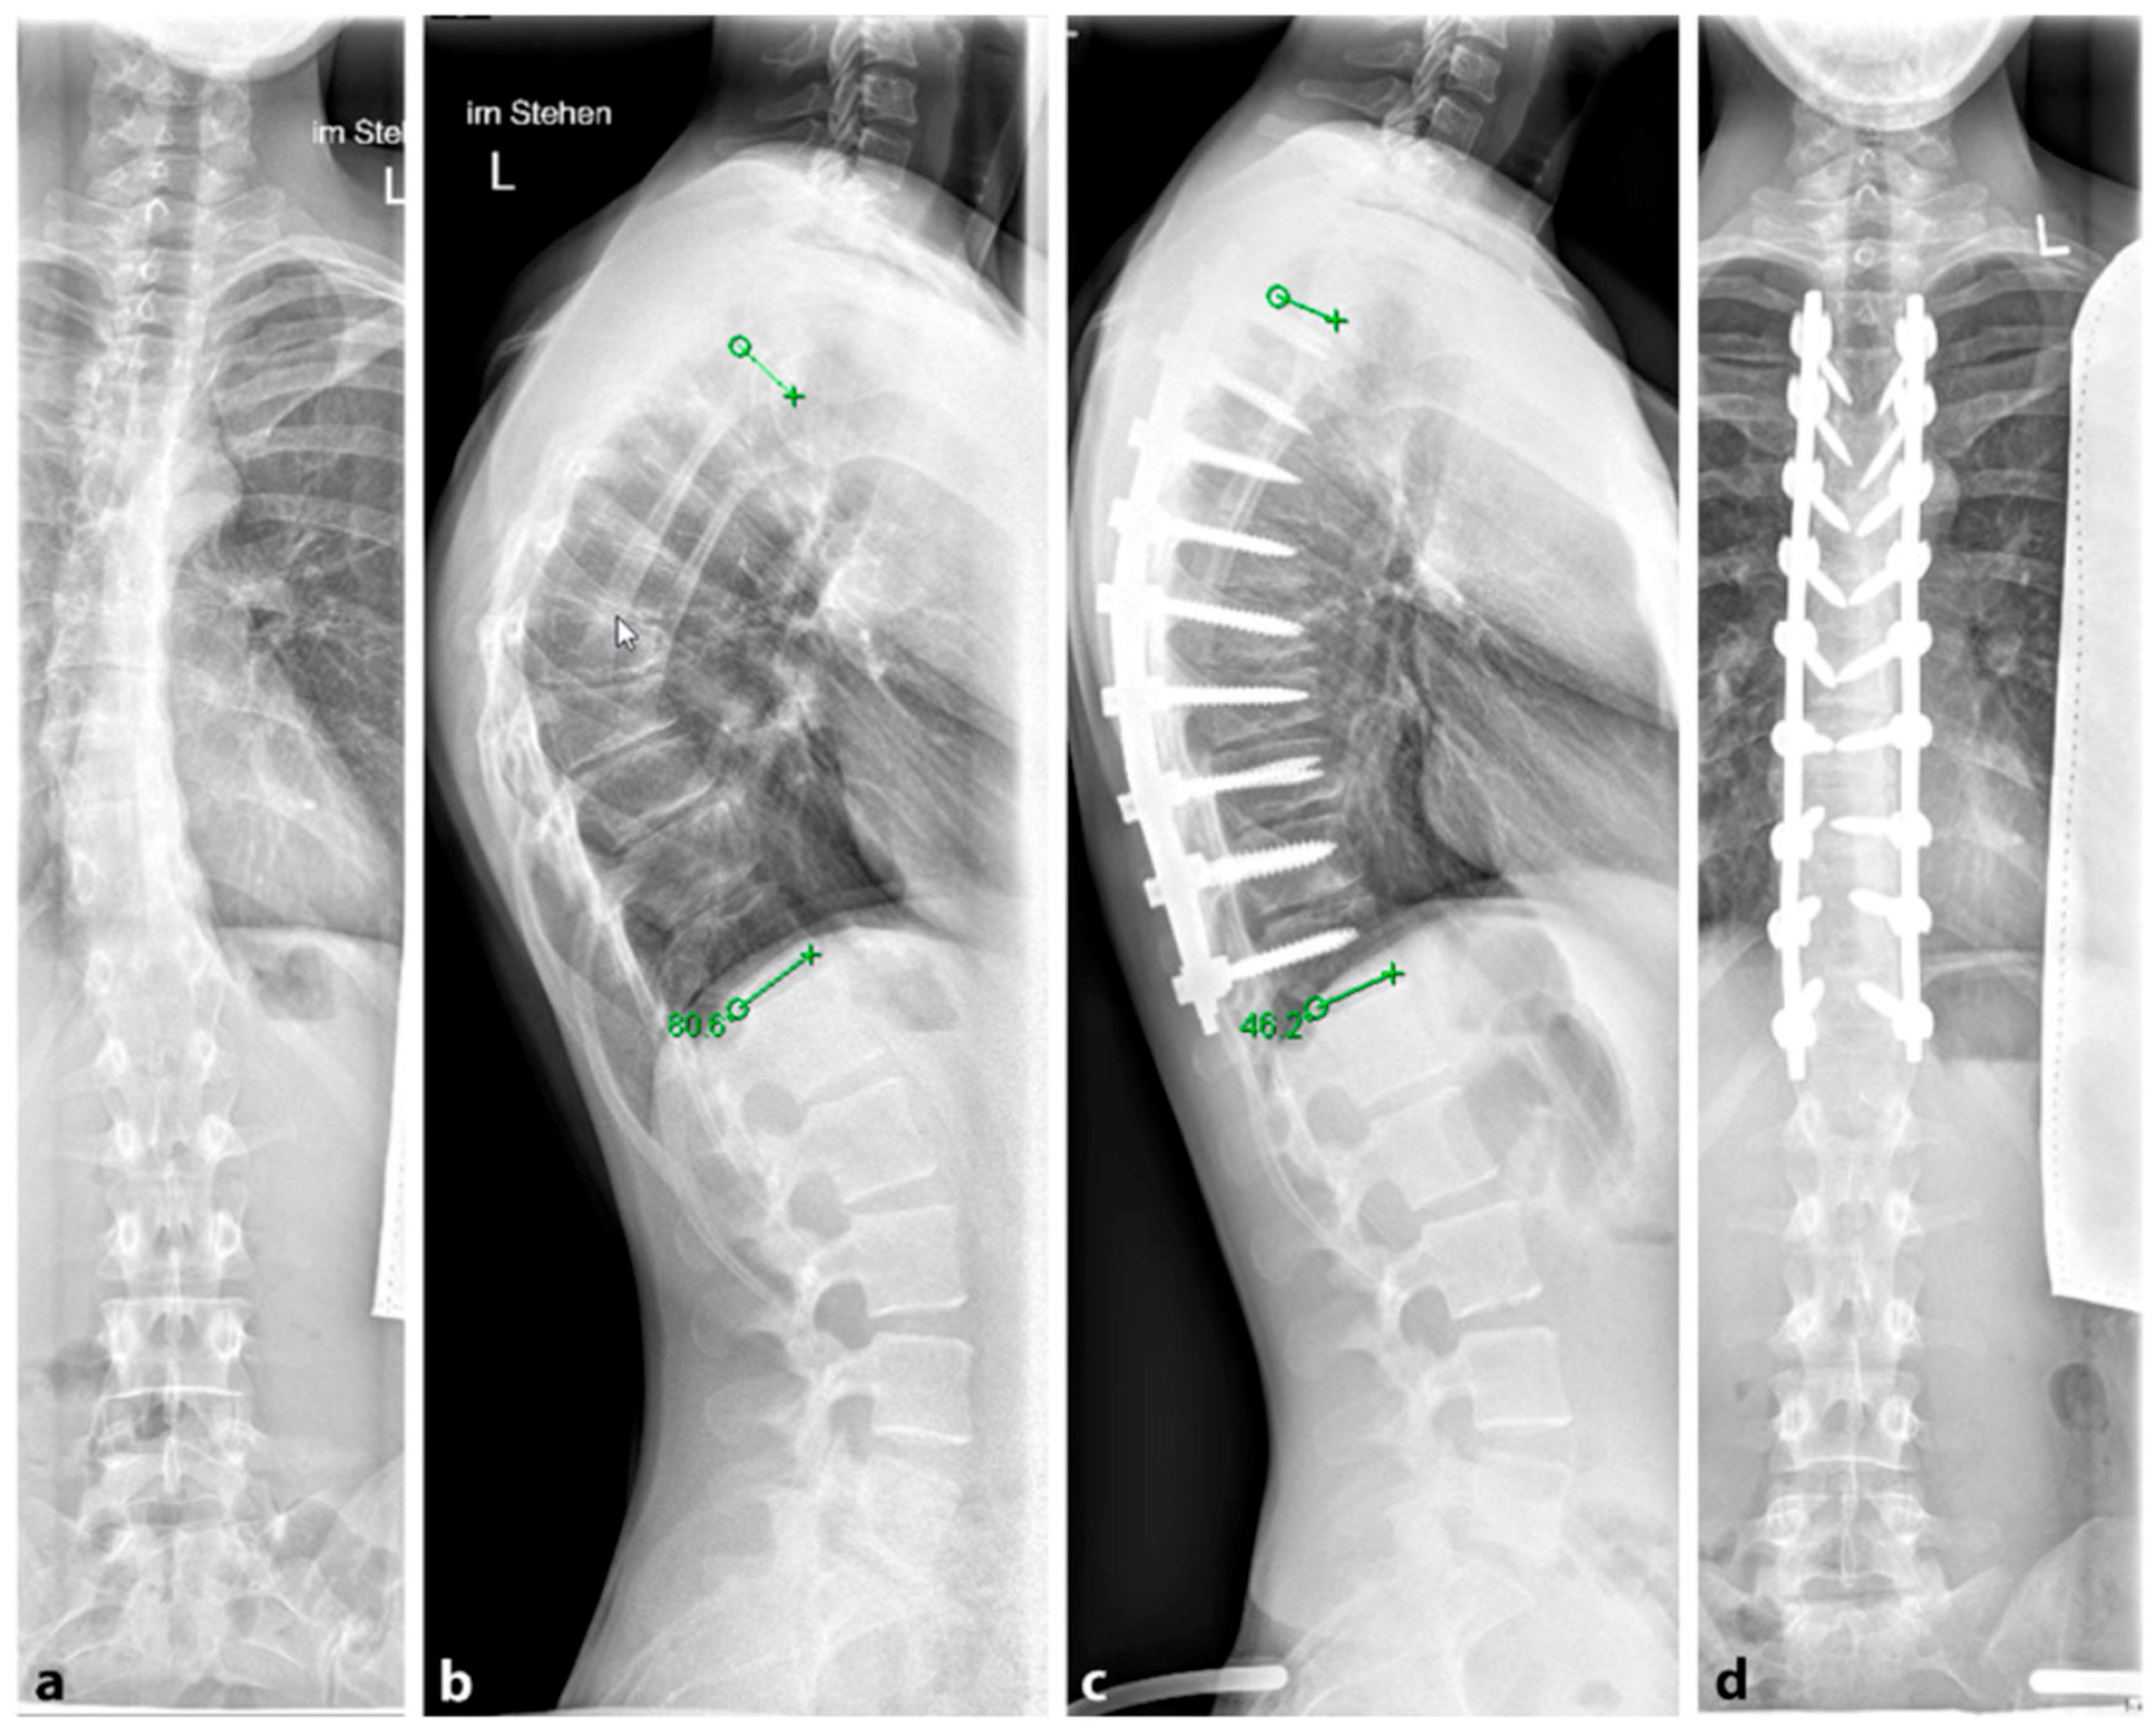

Several surgical techniques have been proposed to address SD, all of which involve three key steps: release of spinal structures, correction of the kyphosis (aiming for at least 50% correction), and spondylodesis with instrumentation [96]; see Figure 11. Some techniques include an anterior release to facilitate posterior curve correction, but the potential benefits of this approach remain uncertain, and it may lead to a higher occurrence of unfavorable effects such as higher complications rates, blood loss and operation time [98,99,100]. Earlier studies have shown favorable outcomes in terms of pain relief and spinal deformity correction following surgical intervention for SD with the most common complications reported being neurological (such as paraplegia), infectious, and respiratory in nature [93,95]. For rigid curvatures, anterior release followed by dorsal instrumentation and spondylodesis was the method of choice until about 20 years ago. However, in several studies, dorsal instrumentation with osteotomies and shortening of the dorsal column achieved comparable results to anterior–posterior procedures [101,102]. Lee et al. evaluated 17 studies and a total of 1147 patients in a meta-analysis. Here, the correction of the kyphotic malalignment between dorsal instrumentation with osteotomies and anterior–posterior spondylodesis was comparable [103]. Despite this, anterior release, fusion and posterior spinal fusion experienced significantly more complications than the posterior spinal fusion alone [101]. Therefore, it is not recommended to subject the patient to additional surgery (i.e., anterior release and fusion). A single posterior approach is adequate to achieve sagittal correction with a balanced spine and fewer associated complications.

Figure 4. (a,b). Preoperative representation of the scoliosis and (c,d). Postoperative image following expansion thoracoplasty and implantation of the vertical expandable prosthetic titanium rib (VEPTR), attached proximal to the rib and distal to the laminae (reprinted with permission [10]).